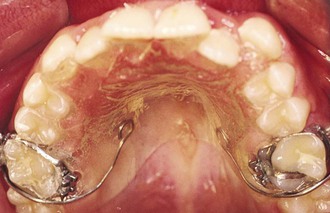

The protraction headgear force is applied via elastics to teeth or other devices supported by teeth and/or the palate. The primary aim is to transmit the force to the midface sutural interfaces. To achieve this, it is important to stabilize the maxilla as one unit (Fig. 16-1). In the primary dentition, it is advisable to use a cemented acrylic occlusal bite block or a removable acrylic plate with occlusal coverage (see Chapter 12). In patients with the mixed dentition and early permanent dentition, a removable acrylic plate (Fig. 16-2) should be used, supported by bands with headgear tubes on the molars or a rigid archwire with a palatal arch. Probably the best stabilization in patients with maxillary first molars is provided by a fixed rapid palatal expansion (RPE) device (Fig. 16-3). We prefer a Hyrax type of nonbonded device, as bonded RPEs (Fig. 16-4) interfere with the primary exfoliating teeth or teeth in the eruptive phase. Studies have also indicated that a simultaneous sutural expansion with an RPE at the start of protraction headgear treatment facilitates the anterior movement of the maxilla.19,20,26,27

Figure 16-2 Occlusal view of a removable intraoral stabilization appliance. The acrylic plate has a clasp that fits on a molar tube of a cemented band. This plate must be worn when the protraction appliance is in use.